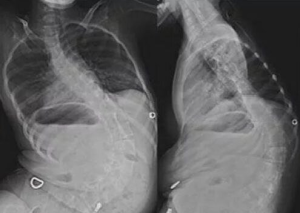

Первым зарегистрированным препаратом, предназначенным для патогенетической терапии СМА, стал нусинерсен, производимый компанией Biogen (США). Первые клинические испытания с участием детей со СМА были проведены в 2016 г., на основании их результатов начаты исследования ENDEAR [11], CHERISH [12] и NURTURE [11]. В исследовании ENDEAR [11] приняли участие дети с диагностированной СМА I типа и двумя копиями гена SMN2 в возрасте до 7 мес. на момент включения в исследование. Исследование было прекращено досрочно в связи с тем, что в результате промежуточного анализа выявилось более значимое улучшение двигательных функций в группе, получавшей лечение, чем в контрольной группе. Во время приема препарата у пациентов отметились клинически значимые сдвиги в виде улучшения двигательных функций, эти пациенты могли удерживать голову, переворачиваться, сидеть без посторонней поддержки, также улучшилась общая выживаемость за период исследования, снизилась потребность в дыхательной поддержке. В исследовании CHERISH [12] приняли участие дети с диагностированной СМА II типа в возрасте от 2 до 12 лет. В результате исследования также были отмечены значительные улучшения двигательных функций у пациентов, получавших лечение. Результаты этих двух исследований стали основанием для одобрения нусинерсена как первого доступного препарата для лечения СМА. Нусинерсен был одобрен к применению у пациентов со СМА всех возрастов в 2016 г. в США и в 2017 г. в Европейском союзе. Он является антисмысловым олигонуклеотидом, который после введения взаимодействует с определенной последовательностью в 7-м экзоне РНК SMN2, тем самым корректируя ошибку в сплайсинге и стимулируя синтез полноценного белка SMN [13]. Препарат одобрен в России для применения у пациентов со СМА в августе 2019 г. [14]. Нусинерсен предназначен для интратекального введения, это более действенный для доставки лекарственного вещества способ, поскольку антисмысловые нуклеотиды плохо проникают через гематоэнцефалический барьер, и если вводить препарат системно, то для достижения терапевтического эффекта потребуется повышение дозы примерно в 100 раз.

Регулярная терапия замедляет течение заболевания и улучшает качество жизни пациентов. Положительной стороной препарата является его доказанная эффективность, отрицательной — интратекальный метод введения, поскольку подобный метод не подходит пациентам с выраженным сколиозом, ротацией позвонков, а также носителям металлоконструкций [15].